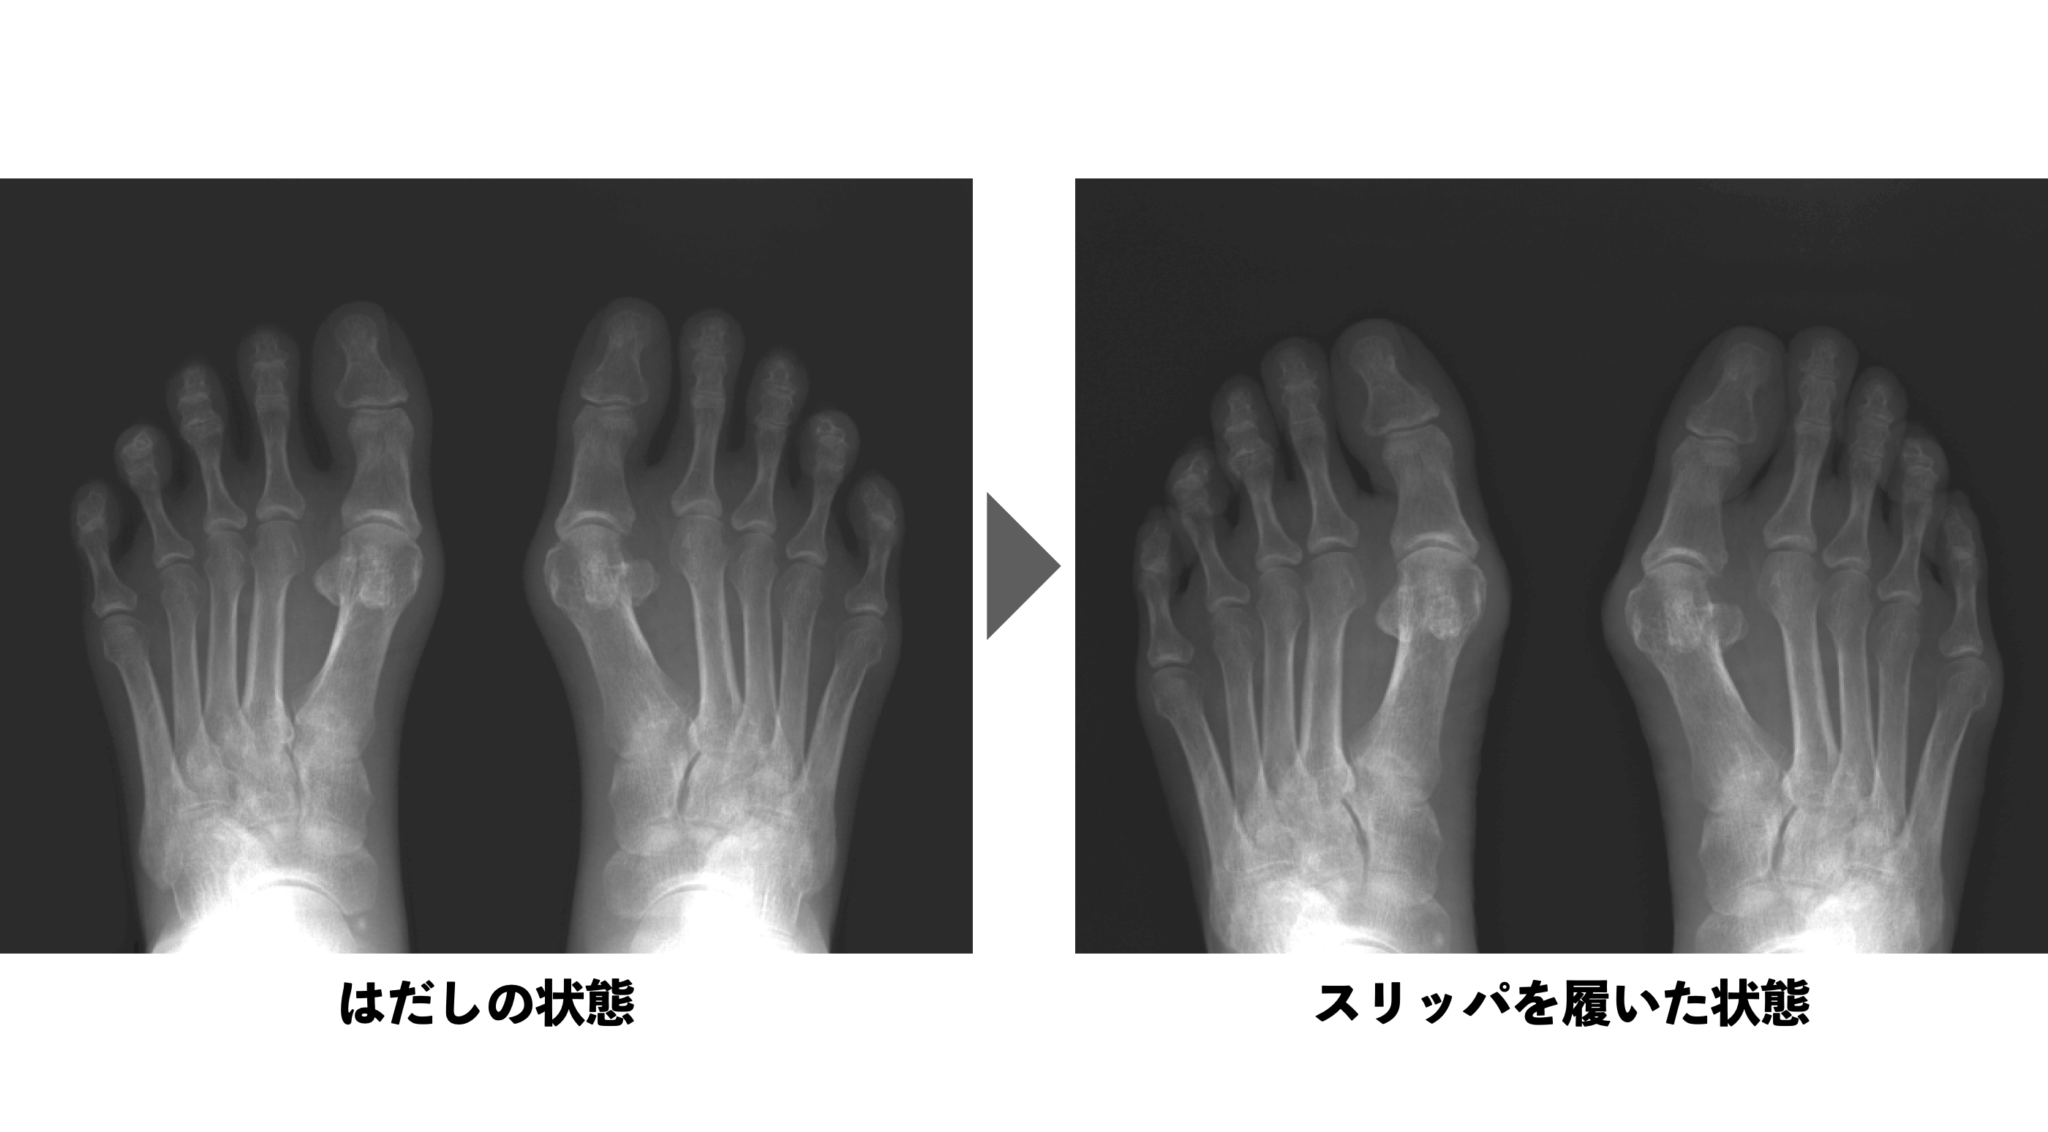

原因① 靴の中で足が「滑っている」

意外かもしれませんが、内反小趾の最大の原因は「靴の中で足が滑ること」です。

実際に足が滑る原因はさまざまですが、もっとも多いのは靴紐が緩いことです。ひも靴でも「甲が締まっていない」「踵が浮いている」などの状態では、足が靴の中で前後・左右にズレてしまいます。

また、以下のような履き物にも注意が必要です。

これらに共通するのは、足首や踵を固定できないため、常に足が前方へ滑ってしまうことです。

その結果、足指で無理に止めようとする「屈み指」や「浮き指」が進行し、筋肉バランスや骨配列に悪影響を与えるのです。

そうすると足趾の支持力が失われ、足裏全体で体重を受け止められなくなるため、筋力の低下と横アーチの崩壊が加速していきます。

結果として、第4〜5中足骨の間隔が広がり、小趾を内側に引き寄せるトルクが増大し、内反小趾の進行に繋がるのです。

YOSHIRO足が靴の中で滑ることで、横アーチ(中足骨アーチ)が次第に潰れ、開帳足になります。このとき、第4〜5中足骨の間隔(IM角)が広がるため、小趾を内側に引き寄せるトルクがさらに強くなり、時間をかけて内反小趾が進行していきます。

最新の臨床レビュー(DiDomenico L, Gatalyak N et al., Clin Podiatr Med Surg, 2013)では、内反小趾の多くに「第4–5中足骨間角(4–5 IMA)の拡大」=横アーチの広がり(開帳足的変化)がみられると報告されています。同時に、第5中足骨の外側偏位や側方湾曲といった構造的変化も高頻度に観察されており、靴内での滑りや外側荷重が続くことで、これらの骨配列異常が進行していくと考えられます。

(出典:DiDomenico L et al., Clin Podiatr Med Surg. 2013;30(3):397–422)

さらに、Shimobayashi M ら(2016)のX線形態学的研究では、bunionette変形を有する足で第5中足骨の外側弯曲(bowing)や外側偏位、そして前足部の横方向拡がり(splaying of the fifth metatarsal)が明確に観察されたと報告されています。つまり、内反小趾では単に小趾の位置がずれるのではなく、足の横アーチ全体が拡がる構造的変化(=開帳足的変化)が起きているのです。